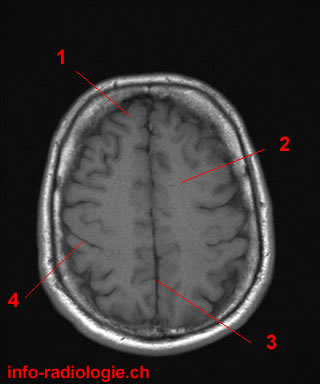

19. What is the medical term for a groove that separates the two hemispheres of the brain?

The interhemispheric fissure is also known as the longitudinal cerebral fissure, which is the deep groove that separates the two hemispheres of the brain. The other options do not specifically refer to this brain structure.